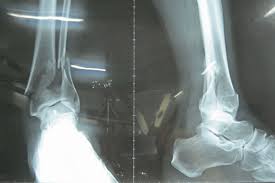

Ngày nay, với sự phát triển của khoa học kỹ thuật, việc chẩn đoán dấu hiệu gãy xương mắt cá chân khá dễ dàng. Bác sĩ sẽ chụp X-quang quanh khu vực mắt cá chân của bạn và đưa ra các kết luận cuối cùng.